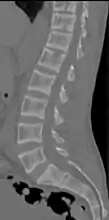

X-ray of a subtle "rugger jersey spine" due to sclerotic bands adjacent to the vertebral endplates.[18]

CT scan of the same case.[18]